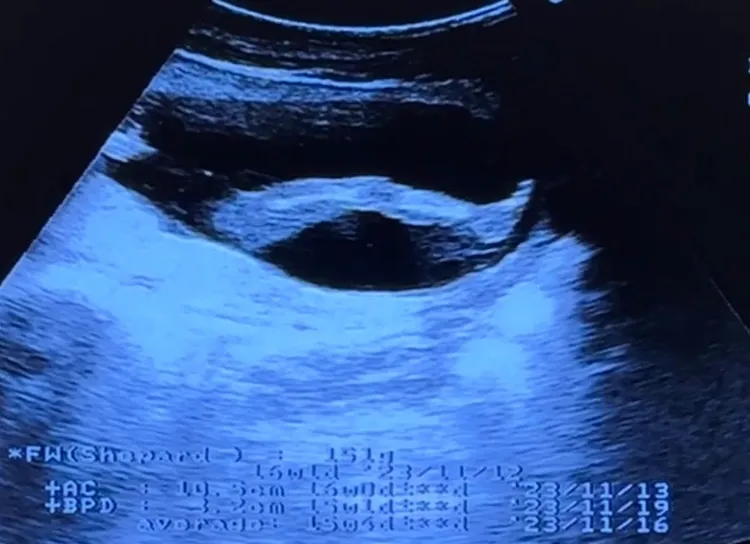

她的預產期預計在今年底或明年初,她表示,希望剖腹產,因為深怕「吃全餐」,談到孕後的身體變化,她透露懷孕初期吃了就吐,吐了就再吃,沒變瘦,反而胖了10公斤,近來她開始游泳及瑜伽,加上她過去準備的懷孕資料,希望肚子的寶寶健康、平安長大,至於乳名,她笑說,因為不知道寶寶的個性,暫時叫「寶寶」、「小呱」,而老公相當開心新生命的到來,賣力工作賺奶粉錢。